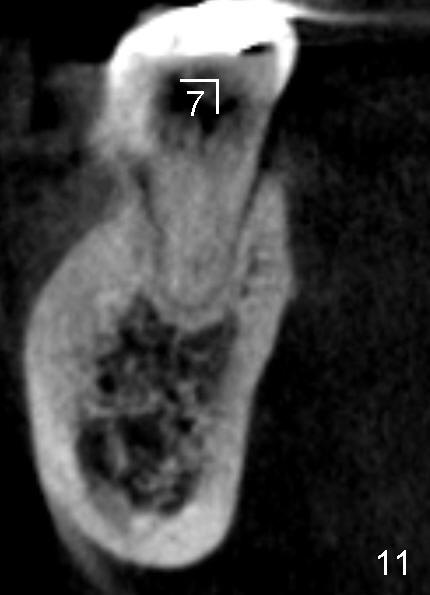

The submandibular (gland) fossa, or lingual (L) concavity (Fig.1 <), is more pronounced in the lower 2nd molar (7) that that of the first (6) (Fig.1 vs.2, 4 vs.3, the same patient). The lingual concavity may be mild (Type I, <2 mm depth, Fig.9-11), moderate (Type II, 2-3 mm, Fig.1,4, 12) and severe (Type III, >3 mm, Fig.13,14 (same patient)).